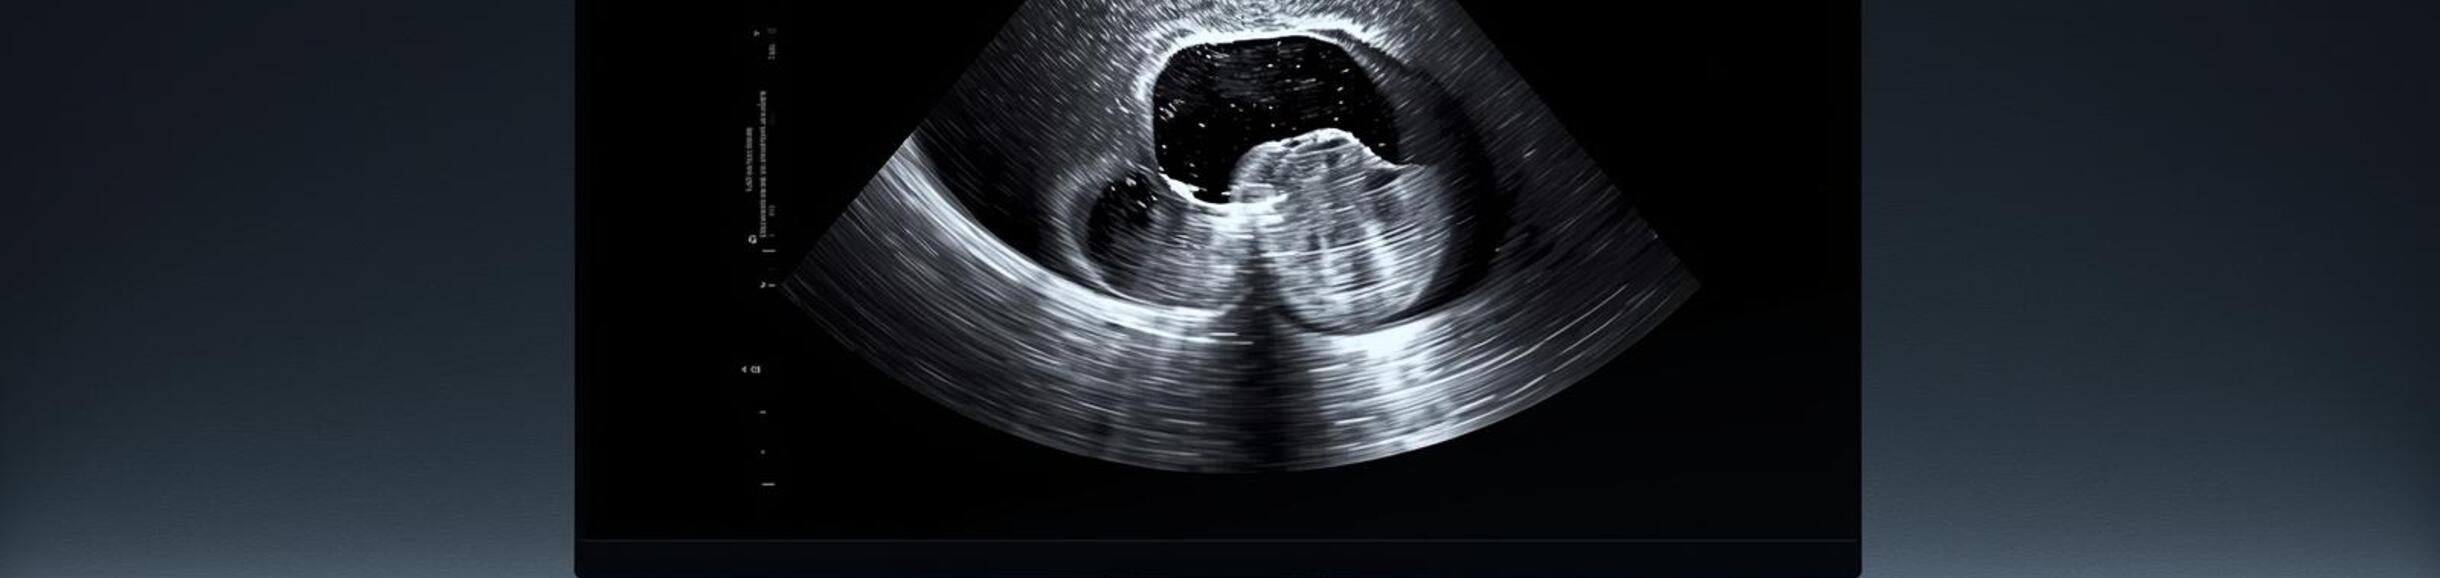

Ultrasound of a baby in utero